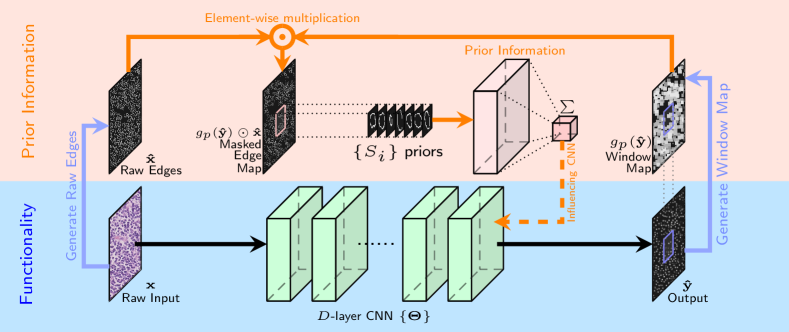

where the term denotes the max pooling operation on with window size , represents element-wise multiplication, and is the 2D convolution operation. Based on Eq. (2), the computation of the shape priors cost term consists of three steps as shown in Fig. 2’s prior information (orange) part:

1.

The CNN output is first thresholded by to eliminate the background noise (Fig. 3-(e)) and then max pooled by with stride of 1 and the ‘SAME’ padding scheme333Because there is no change in the image grid, this is similar to the box-filtering operation in image processing.. This results in a window map that has window centered at each location within the soft detected region (Fig. 3-(c)). As expected, a window with higher numerical value will result if the detected label values (in ) are correspondingly higher (closer to 1).

2.

The window map is then multiplied with the raw edge image element-wise. This step serves to mask out the edges from that surround the detected location in , as shown in Fig. 3-(d).

-

3.

The masked edge image is convolved with the shape priors in set to generate a measurement of how well does the detection fit inside the nucleus shape. If has more labels predicted inside the nucleus boundary, Eq. (2) will achieve a smaller value (more negative).

Note that the effect of the shape prior is captured by a negative regularization term since the goal is to maximize (and not minimize) correlation with ‘expected shapes’. Overall, the cost function of the SP-CNN is given by:

| (3) | ||||

where is the trade-off parameter between the squared loss term and the regularizer representing the effect of the shape prior. The term is carefully designed to simultaneously accomplish two tasks: 1.) a high detection rate of nuclei is encouraged since the element-wise Hadamard product highlights edge boundaries, and 2.) the subsequent convolution with the expert provided shape set reduces false positives. Note that , thus the shape prior cost term is effected by the network parameters and also introduces gradient terms that updates the network parameters during the training process using back-propagation [34]. This is indicated in Fig. 2 by dashed line under “Influencing CNN”. Note that while the black, orange, and blue arrows are used during training, the black arrows are just used in testing stage.